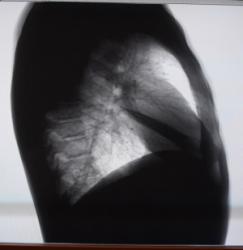

На флюорограмме (Рис.4) определяется негомогенное, интенсивное затенение нижнего и среднего этажа левого легочного поля с косой четкой верхней границей по нижнему краю переднего отрезка III-го ребра. На фоне затенения не дифференцируется левая половина диафрагмы и левые реберно-диафрагмальные синусы.

Рис.4 Рис.5